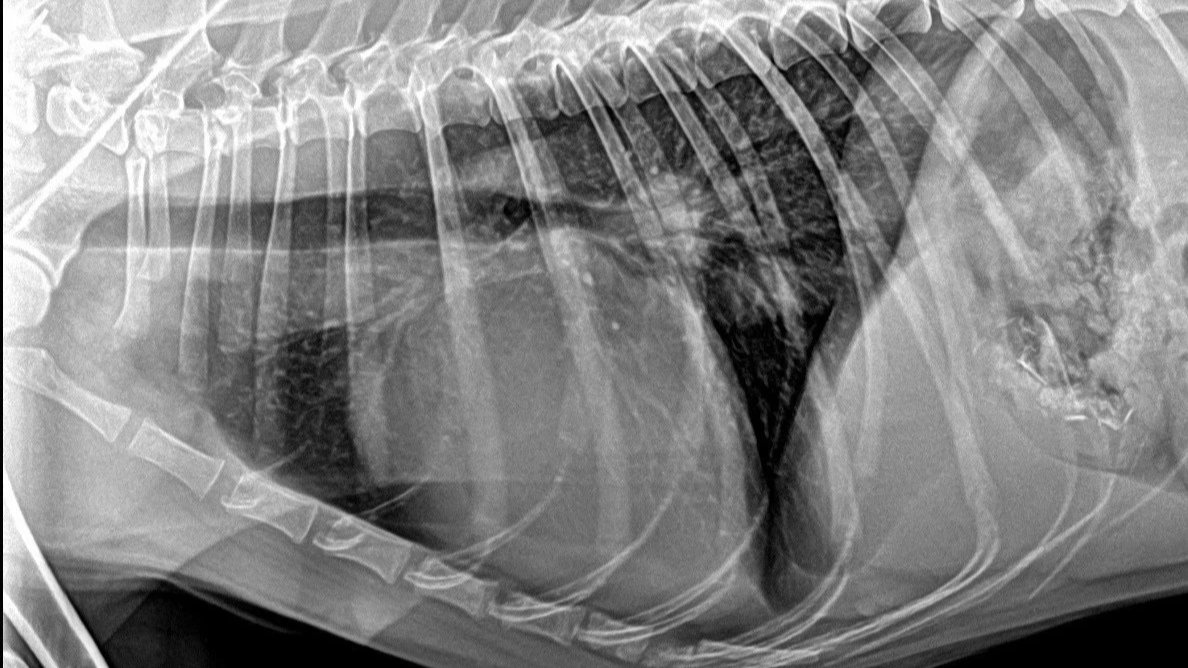

心血管門診

不只喘咳、有時突然昏迷、抽搐也是心血管問題,術前評估心臟功能也很重要!

整合X光與彩色督卜勒超音波,針對心臟腔室,血液動力學做出完整測量提供最準確、有效的心臟病治療方案,有效控制心臟衰竭,同時提供手術病患麻醉前的心臟評估,手術更安全,老年動物也能放心接受手術治療,得到更好的生活品質。

癌症、肝腎疾病、心臟衰竭、糖尿病、白內障青光眼等,威脅熟齡毛孩的健康。安可秉持早期發現早期治療的理念,邀請全齡毛孩定期健康檢查,提高疾病治癒機率,守護合理生活品質。